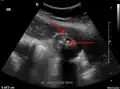

Right upper quadrant abdominal ultrasound is most commonly used to diagnose cholecystitis.[1][26][27] Ultrasound findings suggestive of acute cholecystitis include gallstones, pericholecystic fluid (fluid surrounding the gallbladder), gallbladder wall thickening (wall thickness over 3 mm),[28] dilation of the bile duct, and sonographic Murphy's sign.[13] Given its higher sensitivity, hepatic iminodiacetic acid (HIDA) scan can be used if ultrasound is not diagnostic.[13][14] CT scan may also be used if complications such as perforation or gangrene are suspected.[14]

29. ^ a b "UOTW #30 - Ultrasound of the Week". Ultrasound of the Week. 23 December 2014. Archived from the original on 9 May 2017. Retrieved 27 May 2017.